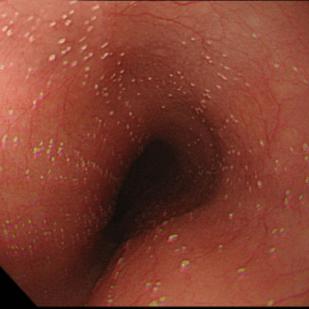

Эндоскопическая классификация кандидозного эзофагита по Kodsi

Степень I: Несколько приподнятых белесоватых бляшек размерами до 2 мм в диаметре, с гиперемией, но без отека или язв.

kandidoznyy_ezofagit.png   kandidoznyy_ezofagit.png